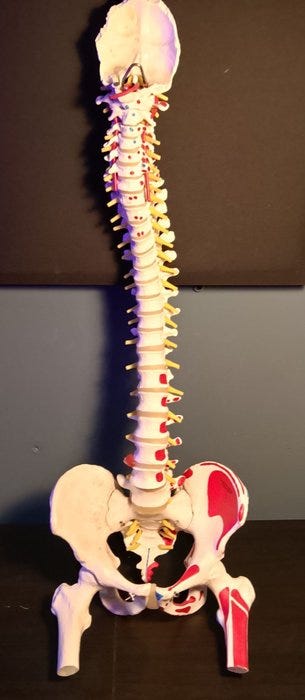

Anatomisk model - Plast - 1990-2000 - Rygsøjlen og hofterne

Plastik kolonne-model i naturlig størrelse, 83 cm høj, 30 cm bred og 20 cm dyb, fra ca. 1990–2000, i god brugt stand med mindre aldersmærker og pletter, i funktion og monteret på en høj kvalitet jernbase. Klik på den blå "gå til varen" knap, for at købe eller byde på denne vare. Den samlede pris vil blive vist inden du afgiver dit bud.

Denne 1:1-naturlige størrelse hvirvelsøjlemodel på 83 cm viser i detaljer alle hovedtræk ved hver hvirvelsøjle, herunder rygraden, nervetråde (nerverødder), vertebrale arterier, intervertebrale skiver, tværgående processer og snit af rygsøjlen. Forskning og studier

Modellen er særligt egnet til visning af en række patologiske misdannelser (rygsøjlens scoliose, lordose, kyfose). Der vises også føle- og spinalender. Den står på en basiskonstruktion. Så kan du levende forklare relevante kundskaber for eleverne gennem modellen, få eleverne til at forstå og hurtigt mestre